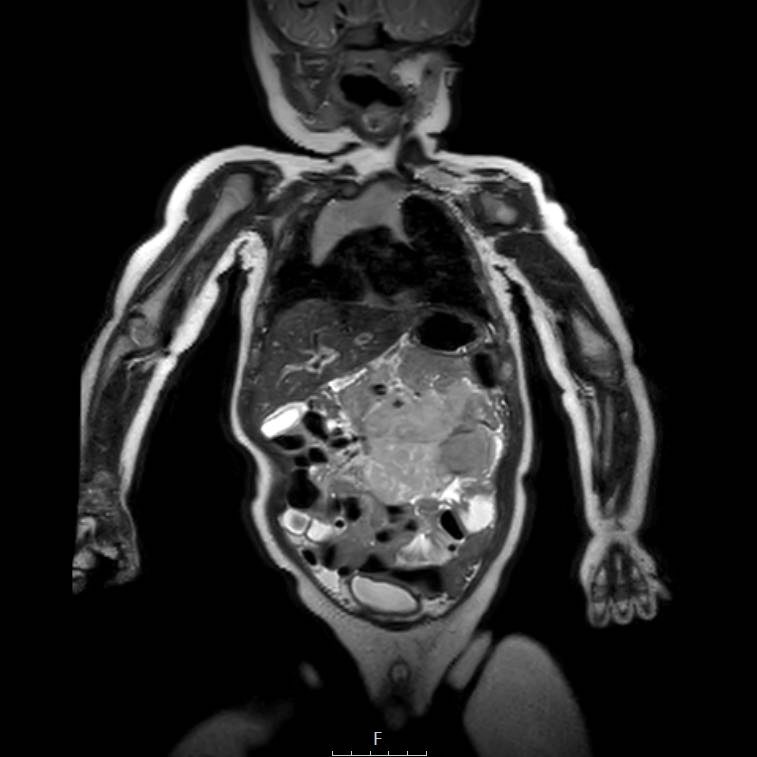

Ví dụ 1

Một bé gái 17 tuổi nhập viện với triệu chứng đau bụng vùng thượng vị. Siêu âm phát hiện một khối u gan lớn.

Trên MRI thấy khối u ở phân thùy gan 5 và 6 với các tổn thương vệ tinh ở phân thùy 7 và 8 (mũi tên). Có huyết khối u trong tĩnh mạch cửa phải (đầu mũi tên) và nhiều di căn phổi (*).